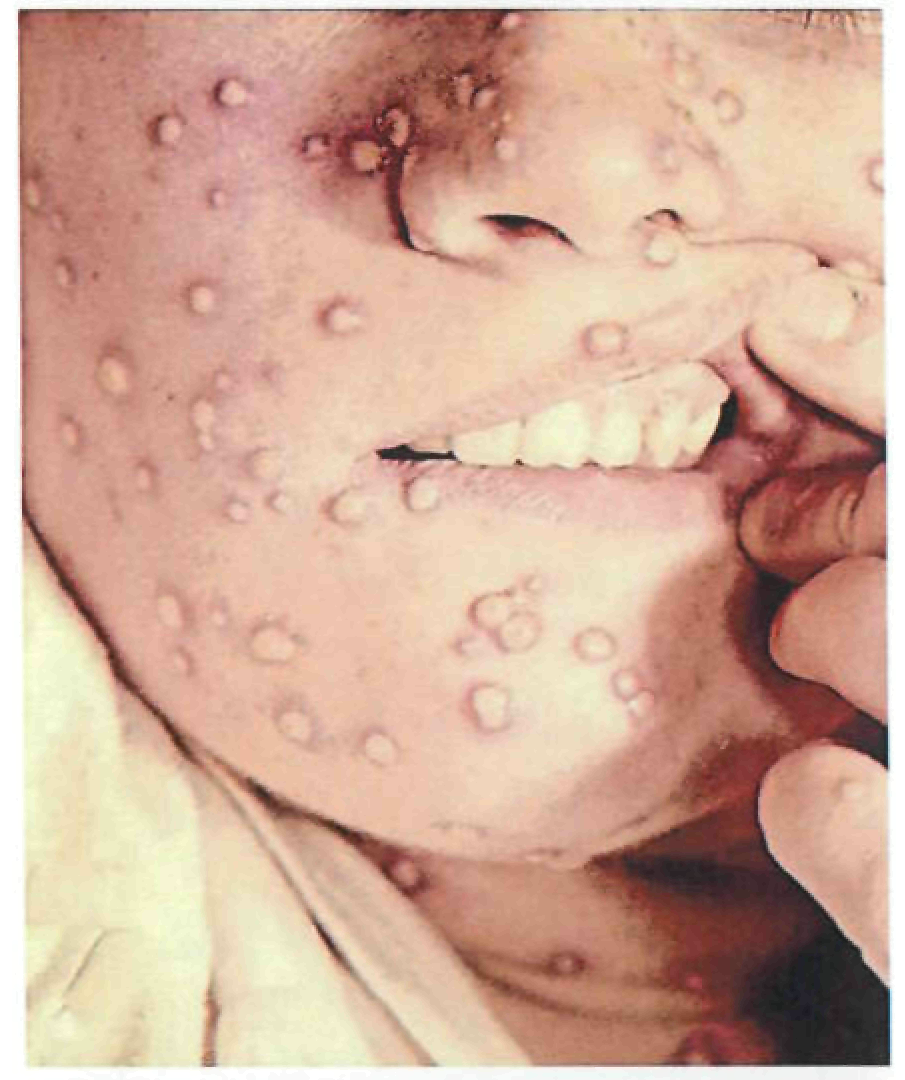

Период высыпаний

На 3-4-й день болезни температура тела снижается до субфебрильной, одновременно на коже головы (прежде всего на лице) и на слизистых оболочках полости рта, гениталий, конъюнктивы, роговицы глаз появляются необильные элементы сыпи. Энантема на слизистых оболочках полости рта обычно предшествует появлению экзантемы. Первые элементы сыпи обычно появляются на лице, быстро распространяясь на верхние конечности, а затем - на туловище и нижние конечности, поражая ладони и подошвы. Распространение экзантемы имеет центробежный характер - на туловище элементов меньше, чем на лице и конечностях.

В 95% случаев сыпь поражает лицо, в 75% - ладони и подошвы, что является отличительным признаком заболевания. Также поражаются слизистые оболочки полости рта (в 70% случаев), половые органы (30%), конъюнктива и/или роговица (20%). У части пациентов имеет место проктит с поражениями перианальной области изолированно или в сочетании с высыпаниями в области гениталий [39]. Количество элементов сыпи варьирует от единичных до нескольких тысяч [13].

При формировании пустул вновь повышается температура тела, нередко до 39-40°С, состояние больных значительно ухудшается, развиваются тахикардия, артериальная гипотензия, одышка, сильный зуд кожи. Возможны диарея, лимфаденит (чаще шейный и паховый).